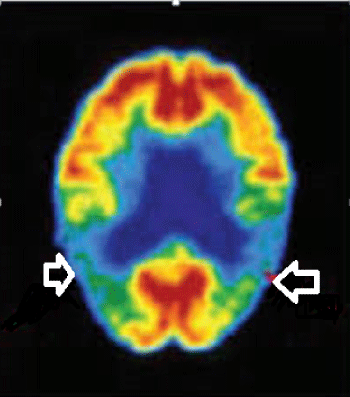

PET- CT: Bilateral temporo-pariet al hypometabolism.

The brain PET-CTs of 21 patients were consistent with AD and bilateral temporopariet al hypometabolism was reported. (Figure 9) PET- CT was inconclusive in 5 cases. Direct communication with the reporting radiologists was arranged.Brain amyloid PET- CT was not done.

Figure 9: PET- CT revealing bilateral temporo-pariet al hypometabolism